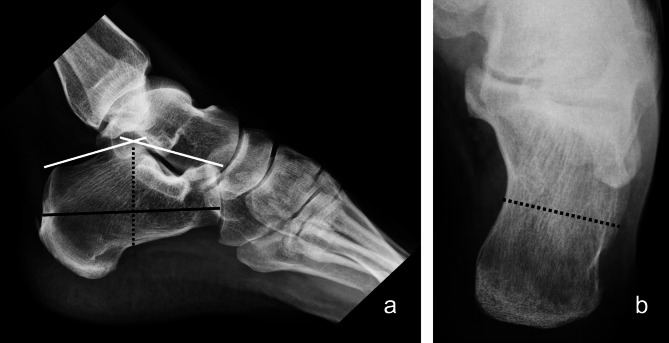

Methods: A total of 38 patients and 40 feet with DIACFs from 2015 to 2020 were retrospectively reviewed with a minimum of 3 years of follow-up. Patients were divided into two groups based on fixation method: minimally invasive locking plate fixation (MIP group) versus screw fixation (SW group) (17 vs 23, respectively). The clinical outcomes were evaluated by the Visual Analogue Scale (VAS), Maryland Foot Score (MFS), Olerud-Molander (OM) ankle score, American Orthopaedic Foot and Ankle Society (AOFAS) hindfoot score, and occurrence of complications. Radiological outcomes were assessed by radiographs for multiple parameters, including calcaneal height, length, width, and Böhler's angle.

Results: The patients were followed up for an average of 63.37 months. There was no significant difference in the final VAS score, MFS, OM score, AOFAS score, and the total incidence of complications between the two groups (P>0.05). Regarding the radiological outcome, there was also no significant difference in the reduction loss of calcaneal height, length, width, and Böhler's angle (P>0.05) after a one-year follow-up period. However, the rate of implant removal in the MIP group was significantly greater than that in the SW group (P< 0.05).